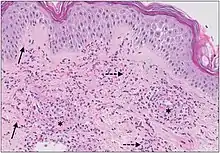

| Urticaria, lymphocyte predominant | Perivascular location. Mast cells are relatively sparse, potentially demonstrated with special stains, preferably tryptase stain. Extravasated erythrocytes are present in about 50% of the cases. No vasculitis.[14] |  Dermal edema [solid arrows in (A,B)] and a sparse superficial predominantly perivascular and interstitial infiltrate of lymphocytes and eosinophils without signs of vasculitis (dashed arrow).[15] Dermal edema [solid arrows in (A,B)] and a sparse superficial predominantly perivascular and interstitial infiltrate of lymphocytes and eosinophils without signs of vasculitis (dashed arrow).[15] |

| Urticaria, lymphocyte predominant | Perivascular location. Mast cells are relatively sparse, potentially demonstrated with special stains, preferably tryptase stain. Extravasated erythrocytes are present in about 50% of the cases. No vasculitis.[14] |  Dermal edema (solid arrows) and a sparse superficial predominantly perivascular and interstitial infiltrate of lymphocytes and eosinophils (dashed arrow) Dermal edema (solid arrows) and a sparse superficial predominantly perivascular and interstitial infiltrate of lymphocytes and eosinophils (dashed arrow) |